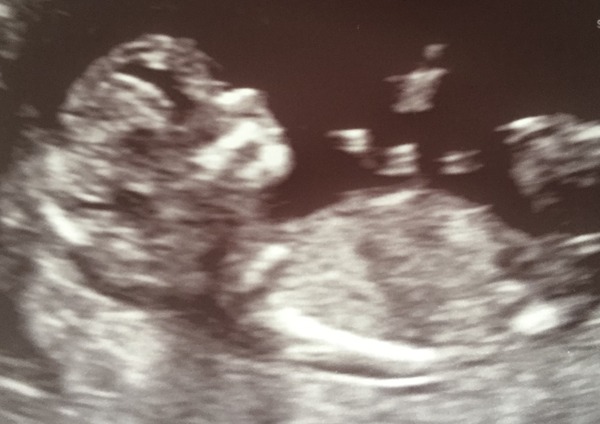

Here is my photo from today. It waved at us. I'm feeling excited now and have been looking on the Internet for baby stuff. I can't remember what we really need and don't need at all

Lovely pic magickal so clear x

magical lovely pic! So clear Smile

Lovely scan magickal how exciting. Is this number 6??! Did I read this correctly?! Amazing!